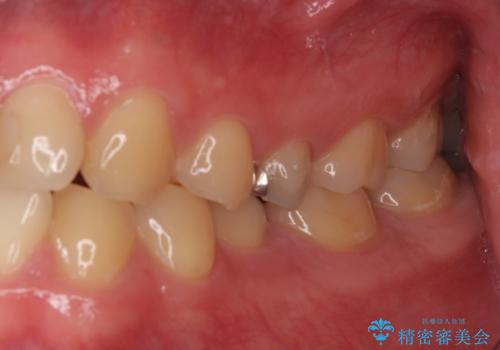

右上もう1本と左上は虫歯治療(セラミックインレー、セラミッククラウン)を行いました。

痛いところがなくなり、患者様には大変満足して頂きました。